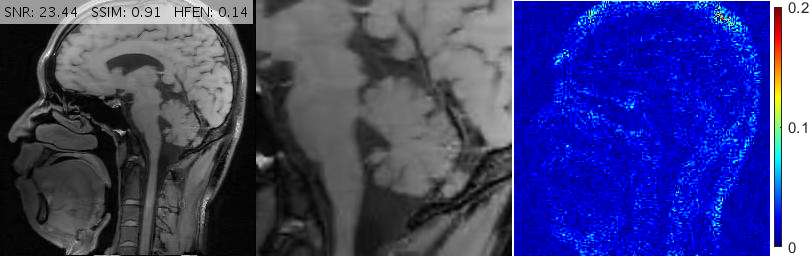

In clinical imaging, the same slice might be acquired in different rotational orientations. For instance, a slice might be imaged in an upright position in one acquisition, but the same slice might be acquired in a rotated position in another experiment. It is ideal to have a robust regularization term that reconstructs the rotated image as if it were acquired in the upward orientation, with no loss of diagnostic value. The rotation-invariance (or isotropy) of RITV was theoretically established in Theorem 2.1. In this subsection we investigate the implication of that result in a rotated imaging setup.

We select a -sized -weighted axial brain scan from our collection along with a 20% Cartesian mask. In order to simulate upright and rotated image acquisition sequences, we consider two setups:

-

1.

The reference image is in upright orientation. The FFT of the image is taken, then the sampling mask is applied (see Fig. 5 (1)).

2.

The reference image is rotated from upright position, say, by (counterclockwise). The FFT is taken, then the sampling mask rotated by the same is applied (see Fig. 5 (2)).

We investigate the performance of RITV compared to TV and TGV in these setups. The implementation of RITV is the same as described in Algorithm 1 and Subsection 3.1, with the only difference being the removal of the BM3D term (and readjustment of to ), since we wish to observe the performance of RITV only. TGV is implemented using the algorithm and parameters described in [7]. TV is also implemented with the same algorithm, with optimized to . TV and TGV algorithms run for 500 iterations while the RITV runs for 200.

Fig. 6 depicts the reconstruction results for above setups. As attested by the magnified views and error metrics inserted to the top of each reconstruction, TV and TGV significantly degrade the reconstructed image in the rotated setup while RITV gives a remarkably consistent and high-quality result which is hardly distinguishable from the upright solution (note that HFEN and SSIM indices do not change in RITV after rotation). Of course, the upright and rotated directions are only chosen relatively and can always be swapped, nevertheless, the point is TV and TGV fail in at least one of the orientations while RITV succeeds in both. Note that if the selected MR image and Cartesian mask are denoted by and respectively, then a simple machine-aided computation shows that . Therefore, even though the norm-preserving assumption of Theorem 2.1 does not hold true in this experiment (and in fact in many practical situations), the result of RITV is still incredibly isotropic.